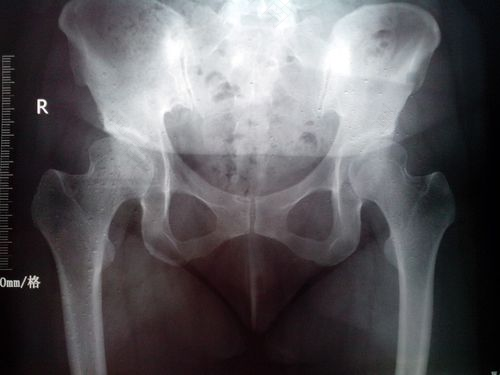

如果是腰椎疾病引发,它可以引发腰腿痛,当然如果是确定,需要通过医生体格检查,根据体格检查情况选择针对性检查,比如x光或ct检查,明确后才做后期处理。现在可以先短期休息,避免长时间站立,行走,坐位,弯腰,自己多按摩,热敷措施,看有无改善。

这种情况考虑坐骨神经痛引起,可以外科检查明确,注意休息,局部按摩理疗等物理治疗,必要时骨外科腰椎检查。

右腿胯骨疼怎么回事?一般情况下,右腿胯骨疼痛是由于坐骨神经或腰椎患病引起的,所以这样的情况对于身体的影响是很大的,在疼痛不是很严重的情况下,可以采取药物结合物理治疗相结合的方式来缓解,尽快使身体恢复健康。在平时注意不能过度劳累,注意身体的保养。